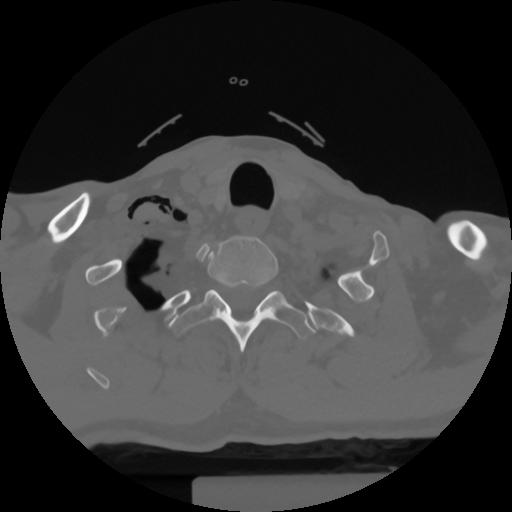

12 P.BLANDAS,,Vol,0.5,P.BLANDAS,,